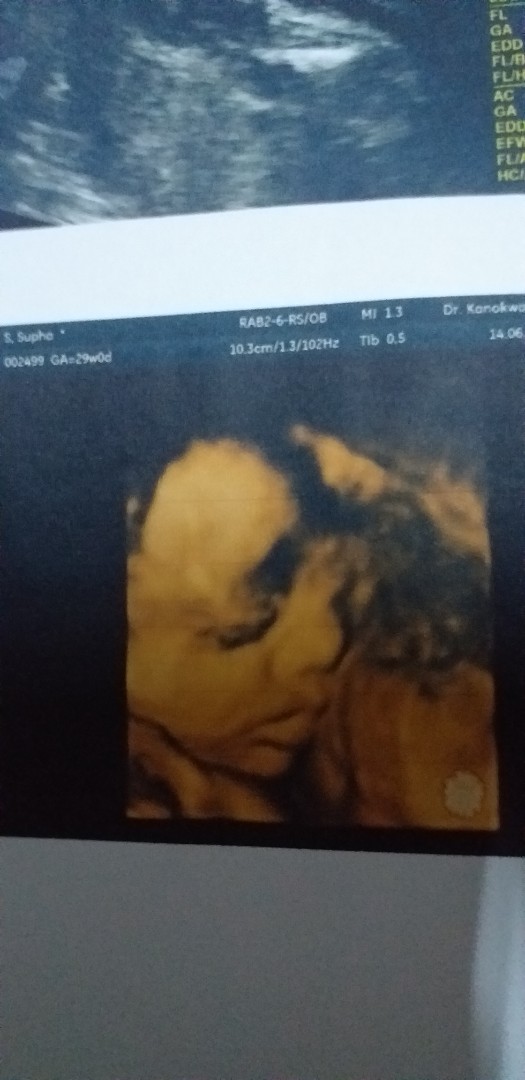

มาอวดภาพแรกของเจ้าตัวน้อยกันคะ

อยากเห็นภาพแรกของเจ้าตัวน้อย. ของแม่ๆ. แต่ละบ้านบ้างอะคะ. มาแชร์ประสบการณ์กันได้นะคะ❤️

29wจ้า

29wแล้วค่ะ